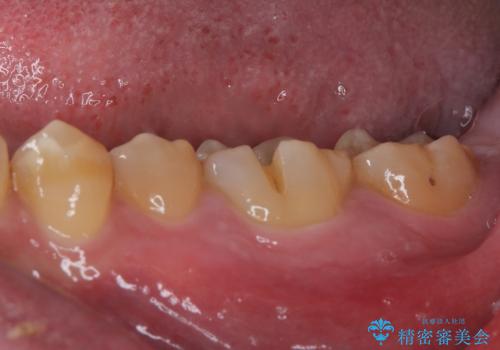

咬合力で破折した奥歯 抜歯即時埋入インプラントによる補綴治療

- 食事中に奥歯が痛むとのことで来院された患者様です。

レントゲンやCTより、深くまで破折していることが分かり、抜歯が必要な状態でした。

歯槽骨の状態は良好であったため、抜歯即時埋入インプラントによる補綴治療を行うこととしました。